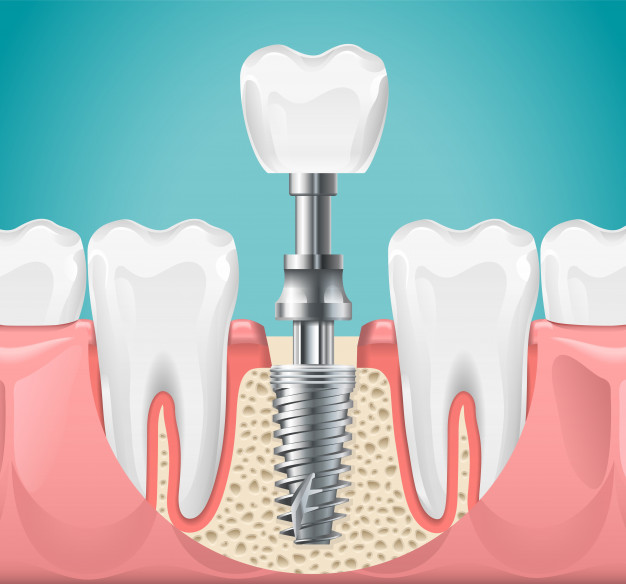

Os implantes dentários são dispositivos feitos em titânio que servem para substituir a raiz do dente e dar suporte a uma prótese, contribuindo assim para uma melhor aparência física e função mastigatória. Eles são indicados para pacientes com perda unitária, parcial ou de todos os dentes.

A forma tradicional de colocação de implante é aquela onde anestesia-se o paciente, com anestesia normal, a mesma que se usa para remover cáries. Após isso, é feita uma incisão com o bisturi, para ter visão da área óssea onde pretende-se instalar os implantes. Depois eles são colocados e realiza-se as suturas para unir novamente um bordo da gengiva ao outro.

Após este processo, aguarda-se de quatro a seis meses na região superior e cerca de dois a três meses na região inferior para que os dentes definitivos possam ser colocados.

No entanto, existe um outro método chamado carga imediata, em que você faz os implantes de manhã e à tarde coloca os dentes provisórios e vai para casa com a boca bonita. Indispensável tomar alguns cuidados com a mordida para que não force os implantes recém-colocados. Porém nem todos os pacientes podem receber a carga imediata. Para que esse procedimento possa ser realizado, você precisa ter osso em boa quantidade de altura e largura e esse osso deve ter uma boa qualidade, também visualizada através da tomografia.

A equipe de cirurgia da Drª Bethania Barros realiza um tipo de cirurgia de implantes sem precisar fazer incisões (cortes), pois os implantes são colocados apenas através de um pequeno furo na gengiva. É o tipo de cirurgia guiada onde é feito um planejamento pelo computador e confeccionada uma guia cirúrgica onde indica ao cirurgião a posição correta que os implantes devem ser colocados. Tornando a cirurgia mais rápida, indolor e com excelente pós operatório.